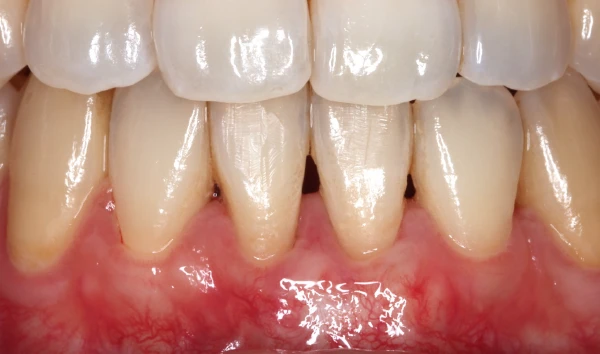

審美歯周病治療

見た目も美しく

歯周病治療を行うと歯茎が下がったとよく聞きます。残念ながら、炎症が長期に渡り存在していた歯茎や、重度歯周病では、治療を行うことにより歯茎が下がり炎症が除去されると歯茎が下がってしましやすいです。そういった場合、セラミックス治療を行うことで審美的に改善を図ることがあります。

また、歯周病はないのに、歯茎が下がってしまうことによる審美性が損なわれてしまう病気があります。そのような場合、歯茎の移植などを行うことにより、歯を削ることなく審美性を改善させることができます。 -